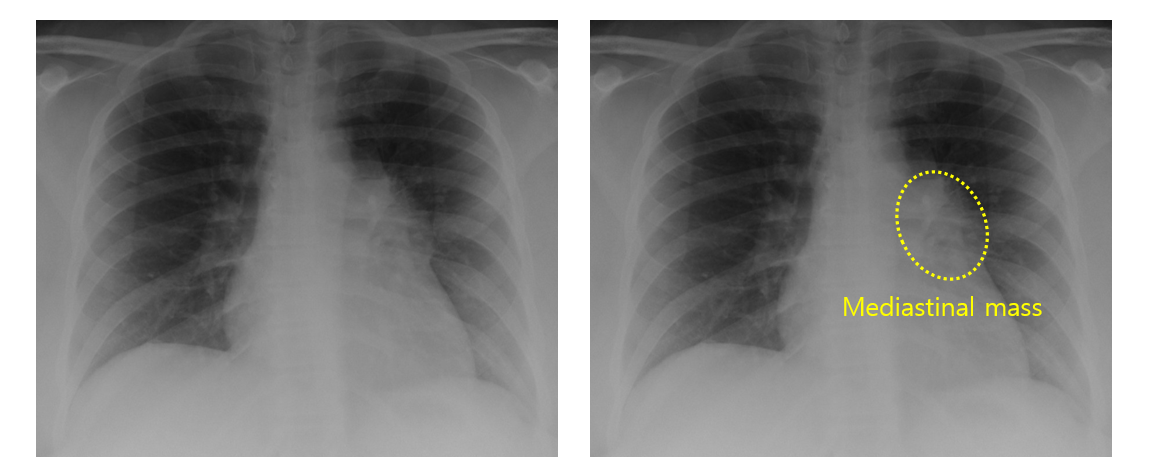

1. 종격동 종괴(mediastinal mass)

① CXR/CT: 1st line